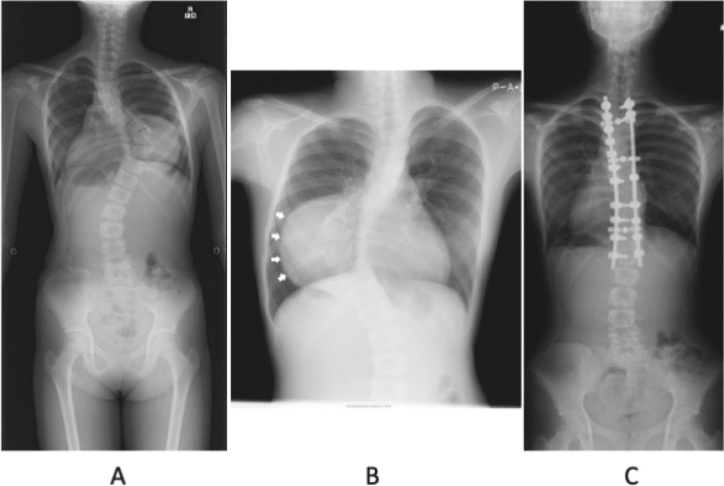

神经节神经瘤是一种罕见的良性肿瘤,起源于交感神经系统。肿瘤的表现是可变的,与青少年胸侧凸有关。在此,我们提出两个病例报告和文献综述。这两例患者分别为10岁和13岁,无肌肉疼痛或无力症状,通过影像学筛查偶然发现神经节神经瘤。两名患者都接受了两阶段的手术。第一阶段涉及肿瘤脱离脊髓,同时从后侧进行畸形矫正手术。第二阶段是通过前路切除神经节神经瘤,没有神经系统问题。两个阶段的手术是必要的切除肿瘤和纠正畸形,从而避免神经问题,同时建立病理诊断。从后路开始被证明是安全且更有效的。

Ganglioneuromas are rare benign tumors that arise from the sympathetic nervous system. The presentation of tumors is variable and associated with adolescent thoracic scoliosis. Herein, we present two case reports and a review of literature. The two cases involved 10 and 13-year-old patients who were asymptomatic for muscle pain or weakness, and ganglioneuromas were incidentally detected through imaging screening. Both patients underwent a two-stage surgery. The first stage involved detachment of the tumor from the spinal cord and simultaneously performing deformity correction surgery from the posterior aspect. The second stage was resection of the ganglioneuroma through the anterior approach without neurological problems. A two-stage surgery was necessary to excise the tumor and correct the deformity, thereby avoiding neurological problems and concurrently establish a pathological diagnosis. Commencing with the posterior approach proved to be safe and was more effective.